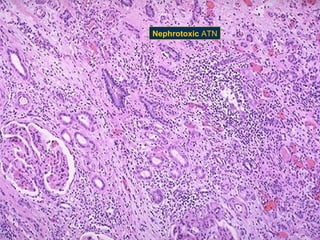

Nephrotoxic ATN

The tubular vacuolization and dilation here is representative of acute tubular necrosis

(ATN(, which has many causes. ATN resulting from toxins as ethylene glycol, usually has

diffuse tubular involvement, while if from ischemia (as in profound hypotension from

cardiac failure( has patchy tubular involvement.